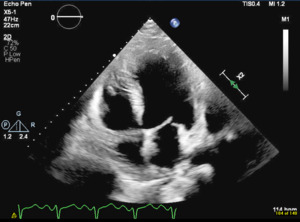

During hospitalization, the patient got a renal ultrasound showing bilateral echogenic kidneys without hydronephrosis. Transthoracic echocardiogram, shown in Figure 1, revealed a left-ventricular ejection fraction of 15-20% with severe global hypokinesis of the left ventricle. He was started on a regimen of hydralazine 50 mg daily, a nitroglycerin patch, and furosemide 40 mg IV once daily. Once he tolerated the nitroglycerin patch without significant side effects, he was switched to combination isosorbide dinitrate/hydralazine. His kidney function stabilized over the preceding days, and he responded well to therapy. Prior to discharge, doxazosin was added for better control of blood pressure. After five days of hospitalization, the patient was discharged with a blood pressure range of 139-163/97-102 mmHg. Furosemide may provide a potential benefit in ADTKD-UMOD, but the patient’s renal function deteriorated significantly during the hospital stay. Furosemide was ultimately withdrawn in hopes of preserving renal function after a collaborative discussion between the cardiologist, nephrologist, and the primary team. His blood pressure medication regimen on discharge was carvedilol 25 mg twice a day, hydralazine-isosorbide dinitrate 37.5 mg/20 mg twice a day (to be up-titrated as an outpatient), and doxazosin 4 mg once a day.

I would like to acknowledge Dr. Zeel Patel in assisting with editing and providing feedback. Thank you to Dr. Qaisra Saeed for providing echocardiogram images.